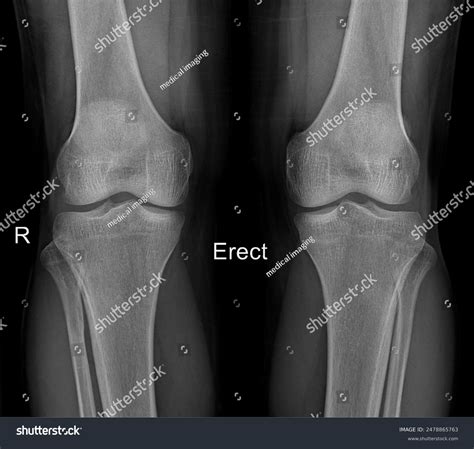

Similarly, diagnosing bilateral knee pain might include:

• X-rays or MRI scans to visualize the joint structure.

Case Study 2: Bilateral Knee Pain

A 50-year-old patient complains of bilateral knee pain, which has been worsening over the past year. Diagnostic tests reveal bilateral osteoarthritis. The treatment plan includes physical therapy, pain management medications, and lifestyle modifications to reduce stress on the joints. Surgical options are discussed if conservative treatments fail to provide relief.